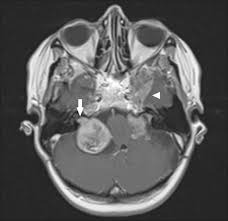

Refer to caption

Figure 1: MRI Scans Showing Various Conditions: Glioma, Meningioma,a Non-Tumor Case and Pituitary Tumor

A few images from each class were visually inspected to understand dataset balance and quality, with examples shown in Figure 1. The varying nature of gliomas, meningiomas, pituitary tumors, and non-tumor cases hence brought a firm rationale before the model building and evaluating stages.